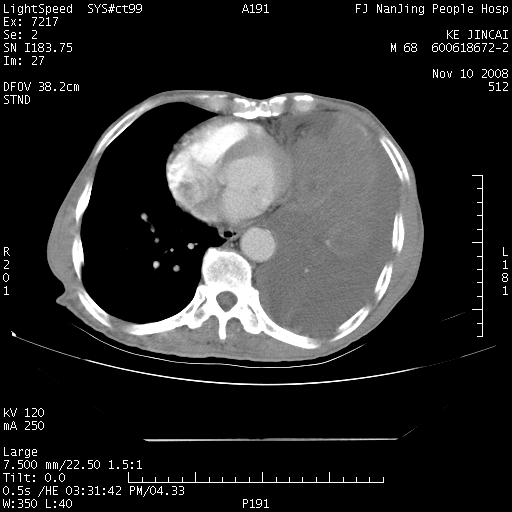

是个很有看头的病例,咋人气那么不旺?没多少人兴趣呢?这个病例几大怪:1   恶性肿瘤侵犯心肌左房怪,心肌一般不会被恶性肿瘤侵犯吧?2   左下肺均匀实变怪,内无含气,有别一般不张实变,含气肺泡完全为液体取代,而非一般不张实变的肺萎陷,冷不丁还以为是肿大的脾脏3   肿瘤本身怪,像tb肺不张4   这么有看头的病例没人气怪。呵呵。

左肺恶性肿瘤侵犯肺动脉,左心房内瘤栓,胸膜转移。

左肺恶性肿瘤侵犯肺动脉,左心房内瘤栓,胸膜转移,少见,学习了。